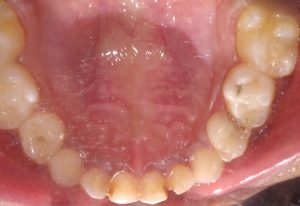

We at the Department of Pediatric & Preventive Dentistry focus on comprehensive oral health care needs of a child from infancy to adulthood and provide comprehensive, therapeutic as well as preventive care to all children including those with special care needs.